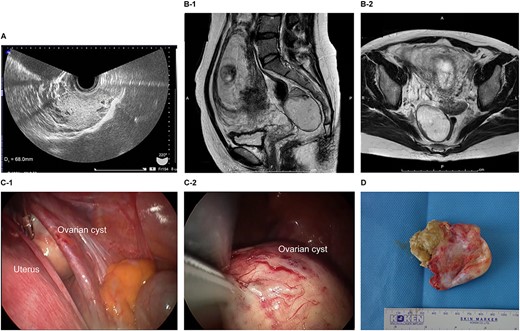

The patient was a 38-year-old, gravida 3, para 1 woman with no familial or medical history. She conceived naturally and was diagnosed at 7 weeks of gestation in another medical facility. She was subsequently referred to our hospital for further examination and operation. Transvaginal ultrasonography (TVUS) revealed a fetus in the uterus and a mass 7 cm in diameter on the right ovary. Magnetic resonance imaging (MRI) revealed right ovarian cystic tumors with fat tissue. The patient’s laboratory values, including levels of tumor markers (e.g. carcinoembryonic antigen, CEA; cancer antigen 125, CA 125; cancer antigen19–9, CA 19–9 and squamous cell carcinoma antigen, SCC), were within the normal limits. The tumor was diagnosed pre-operatively as a dermoid cyst. We performed single-port laparoscopic surgery at 16 weeks and 2 days gestation to remove the right ovarian cysts. The total procedure was performed within 55 minutes, and there were no complications (Fig. 1).

Imaging studies and laparoscopic views and specimen photograph of case 1. (A) Transvaginal ultrasound image showing an ovarian cyst. (B-1) Sagittal T2-weighted magnetic resonance image (MRI) showing an ovarian cyst. (B-2) Axial T2-weighted MRI showing an ovarian cyst. (C-1) Gestational uterus: ovarian cyst was moved from the pouch of Douglas. (C-2) Ovarian cyst was moved and located on the gestational uterus. (D) Ovarian Cyst.